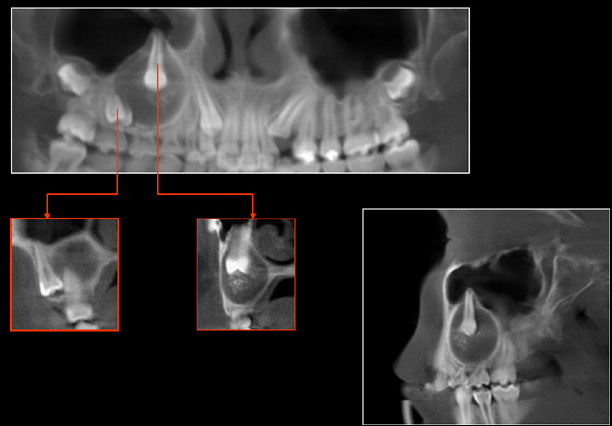

Paciente femenino 14 años de edad,asintomática. Es referida a la consulta para la evaluación radiográfica por persistencia de las piezas 5.5 y 5.4 . A la evaluación intraoral se observa aumento de volumen a nivel apical de las piezas 1.6 , 5.5 y 5.4 de consistencia dura no dolorosa a la palpación, la mucosa que lo recubre se presenta de características normales. Se le realiza el estudio con tomografía volumétrica (Picasso E-WOO),se grafican cortes panorámico, transaxiales, sagital, coronales y axiales, los que muestran una imagen mixta asociada a la retención de la pieza 1.4, que condiciona el desplazamiento hacia distal de la pieza 1.5 que se encuentra próxima a la tabla ósea vestibular y a nivel apical de la pieza 1.6; así mismo apreciamos el desplazamiento hacia mesial de la pieza 1.3, como también la expansión de las tablas óseas vestibular y palatina. Obsérvese la presencia de imágenes hiperdensas alrededor de la corona de la pieza dentaria, compatibles con calcificaciones en el interior de la lesión.